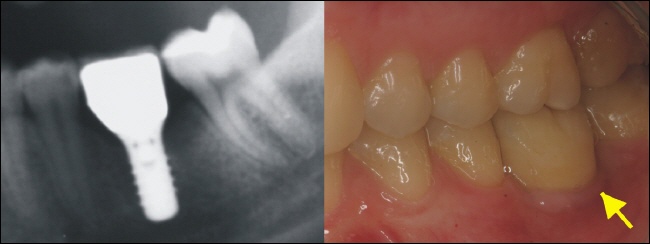

Das Röntgenbild links zeigt den perfekten Sitz der Implantatkrone. Die Lücke ist ohne weitere Schäden an Nachbarzähnen stabil versorgt. Für den Patienten ist die Implantatkrone nun gar nicht mehr zu erkennen und der Zahn im Ganzen nach dem Vorbild der Natur wiederhergestellt.

Der gelbe Pfeil zeigt auf dem Bild rechts, wo sich die Implantatkrone in der Zahnreihe „versteckt“.